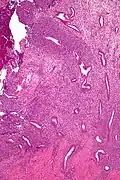

Micrograph of a uterine adenosarcoma showing a mitotically active malignant stroma and benign glands. H&E stain.

Uterine adenosarcoma have, by definition, a malignant stroma and benign glandular elements. The World Health Organization (WHO) criteria have a mitotic rate cut point; however, this is often disregarded, as bland-appearing tumours with a low mitotic rate are known to metastasize occasionally.[2]